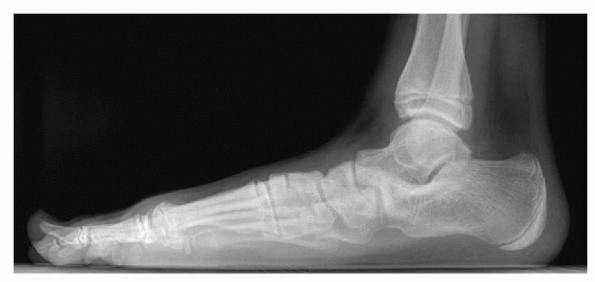

Lateral weightbearing (Fig. 4.4-2):

-

□ Anteater nose (CNC)

□ Talar beaking (not degenerative sign) (TCC)

□ C sign (of Lateur): Initially thought to be a reliable indicator for middle facet TCC but is actually specific for flatfoot, not coalition)

□ Rounding/flattening talar lateral process

□ Concave plantar surface: talar neck

□ Narrowing of the posterior subtalar facet (TCC)

□ Failure to visualize middle subtalar facet (TCC)

![]() |

|

Figure 4.4-2 Lateral weightbearing view of the hindfoot in a patient with a stiff flatfoot caused by a calcaneonavicular coalition.